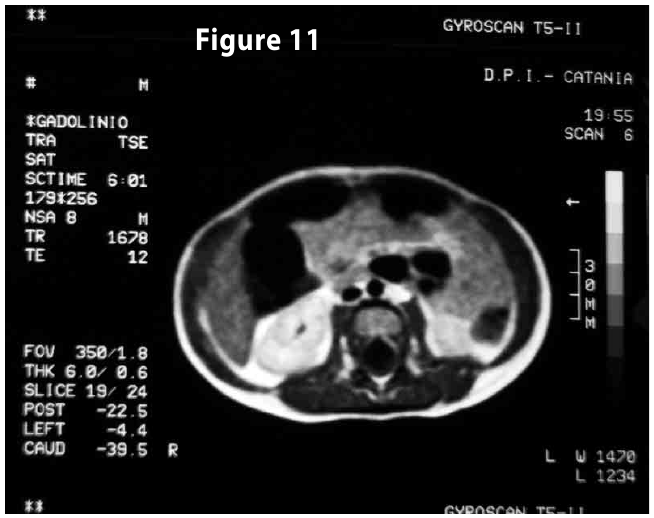

Figure11